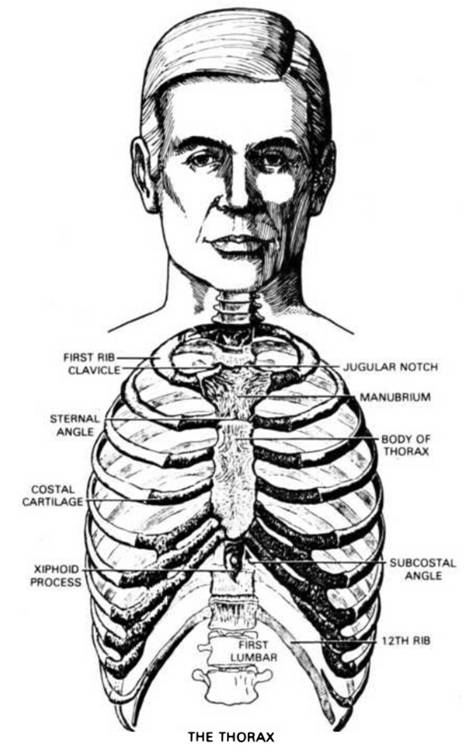

It is my opinion that the most important subject missing in elementary schools, is ANATOMY. This sketch is included here to serve as a guide and handy reference. The numbers indicate the location of the various parts.

1. The Frontal Sinus, in the forehead, above the eye where mucus accumulates eventually when we eat excessive amounts of concentrated starches, and drink too much milk.

2. The Pituitary Gland (or Body) is located directly behind and just a little below the level of the bridge of the nose.

3. The Pineal Gland, located in the mid-brain, back, and slightly higher than the Pituitary.

4. The Tongue, one of the most mischievous organs of the human body.

5. The Medulla Oblongata, the central Nerve-telephone-exchange, is situated in the lower middle part of the head between the upper lip and the base of the skull, just above the Atlas or first cervical vertebra.

6. The Parotid Gland, which becomes swollen and causes Mumps, especially when children and adolescents indulge in excesses of starches and candies.

7. The Sub-Lingual Gland.

8. Sub-Maxillary Gland.

9. The Epiglottis.

10. The Pharynx

11. TheThyroid Gland, one of the most vital and important glands of the body. It requires Iodine-foods for proper functioning. When improperly nourished causes Goiter.

12. The Larynx.

13. The Spleen is located towards the back of number 19. Back of the Ribs at this point are the Lungs; back of the Lungs, the Stomach the Splenic Flexure of the Colon, the Spleen, the tip of the Pancreas and the left Kidney.

14. The Gall Bladder - That most essential, though greatly abused gland. The Liver (No. 15) has been raised in this picture, with a hook, to show its location. Its duct leads into the Duodenum (No. 24) to lubricate the intestines with the bile. To remove a Gall Bladder (instead of cleansing the system naturally) deprives the unlucky individual of Natures means for lubricating the intestines sufficiently.

15. The Liver -The most marvelous laboratory in Creation. Created by Nature to withstand on an average about 40 to 50 years of abuse after birth before perceptible and usually uncomfortable disintegration begins.

16. The Stomach - That organ which controls the Individual, unless the Individual learns to control it.

17. The Pyloric Valve, between the Stomach and Duodenum.

18. The Pancreas, the gland which enables the body to utilize natural sugars (such as are found in raw fruits and vegetables) and which breaks down when refined sugars and starches are used to excess causing diabetes.

19. The Splenic Flexure of the Colon, or the bend in the Colon leading from the Transverse Colon (No. 22 and No. 23) to the Descending Colon (No. 31).

20. The general location (further back) of the Kidneys.

21. The Hepatic Flexure of the Colon, leading from the Ascending Colon (No. 32) to the Transverse Colon (Nos. 23-22).

22. The Transverse Colon, frequently becomes a gas storage balloon when 23 . tense nerves or impactions of waste matter in the Flexures (Nos. 21-29) prevent the gas from expanding and being expelled. Asa result of improper nourishment this section of the Colon easily loses its tone and then sags, causing what is more picturesquely described as a prolapsus.

24. The Duodenum, or Second Stomach, where the alkaline digestive processes we so frequently interfered with by the presence of acid or acid-forming foods with concentrated starches and sugars, often resulting in ulcerous conditions which individuals enjoy calling their Duodenal Ulcers.

25. The area of the Solar Plexus.

26. The Small Intestines, about 25 feet of perpetual trouble sooner or later, for these who insist on eating what they want when they want it.

27. The Appendix, that marvelous safety gland whose secretion prevents gas forming bacteria and other noxious germs from passing into the Small Intestines from the Colon. It has of late been allowed to function more normally since the education of the laity in the use of frequent enemas and skillful colonic irrigations.

28. The Bladder is in this region.

29. The Sigmoid Flexure of the Colon leading from the Descending Colon (No. 31) to the Rectum (No. 30).

30. The Rectum, the cesspool of the body, which should be washed out with enemas or colonic irrigations quite often.

31. The Descending Colon.

32. The Ascending Colon.